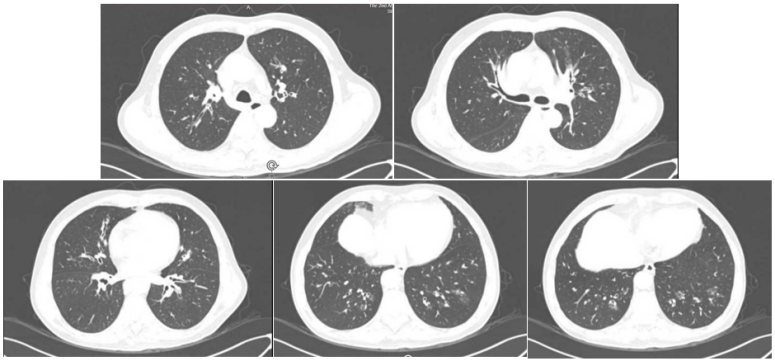

患者男性,51岁,因“咳嗽、咳痰5天,发热伴呼吸困难3天”入院。入院前曾应用静脉激素。既往有胰腺癌病史,入院后发现血糖明显升高,并确诊2型糖尿病。乙型流感病毒核酸阳性。血清GM试验阴性,BALF GM >5 S/CO,曲霉IgG阴性,BALF mNGS提示烟曲霉(序列数809975),乙型流感病毒(序列数2732),BALF培养结果为烟曲霉,对伏立康唑耐药。患者胸部CT及气管镜结果如下图所示。患者,男性,36岁,因“咳嗽、咳痰1周,呼吸困难2天”入院。入院前2天外院诊断糖尿病酮症酸中毒、乙型流感病毒性肺炎,并有使用静脉激素。入院查乙型流感病毒核酸阳性。BALF GM>5 S/CO,血清GM 4.8 S/CO,曲霉IgG阴性,BALF mNGS提示烟曲霉(序列数25173),乙型流感病毒(序列数90),气道假膜钳夹组织及BALF培养烟曲霉。患者胸部CT及气管镜结果如下图所示。IAPA的发病率较高,且在不同的流感亚型中无显著差异。而且IAPA的病死率高,但早期临床表现缺乏特异性,诊断存在一定困难,应引起临床医师的高度关注。早期、准确地识别与诊断IAPA,及时启动抗真菌治疗是改善预后的关键。[1] Iuliano AD, Roguski KM, Chang HH, et al. Estimates of global seasonal influenza‑associated respiratory mortality: a modelling study[J]. Lancet, 2018, 391(10127):1285-1300. [2] Verweij PE, Rijnders BJA, Brüggemann RJM, et al. Review of influenza‑associated pulmonary aspergillosis in ICU patients and proposal for a case definition: an expert opinion[J]. Intensive Care Med, 2020, 46(8): 1524-1535.[3] Martin-Loeches I, J Schultz M, Vincent JL, et al. Increased incidence of co-infection in critically ill patients with influenza[J]. Intensive Care Med, 2017, 43(1):48-58.[4] ABBOTT JD, FERNANDO HV, GURLING K, et al. Pulmonary aspergillosis following post‑influenzal bronchopneumonia treated with antibiotics[J]. Br Med J, 1952, 1(4757):523-525. [5] Martin-Loeches I, J Schultz M, Vincent JL, et al. Increased incidence of coinfection in critically ill patients with influenza[J]. Intensive Care Med, 2017, 43:48-58.[6] Schauwvlieghe AFAD, Rijnders BJA, Philips N, et al. Invasive aspergillosis in patients admitted to the intensive care unit with severe influenza: a retrospective cohort study[J]. Lancet Respir Med, 2018, 6(10): 782-792.[7] Beumer MC, Koch RM, van Beuningen D, et al. Influenza virus and factors that are associated with ICU admission, pulmonary co-infections and ICU mortality[J]. J Crit Care, 2019, 50:59-65. [8] Huang L, Zhang N, Huang X, et al. Invasive pulmonary aspergillosis in patients with influenza infection: a retrospective study and review of the literature[J]. Clin Respir J, 2019, 13(4):202-211. [9] Krifors A, Blennow O, Påhlman LI, et al. Influenza-associated invasive aspergillosis in patients admitted to the intensive care unit in Sweden: a prospective multicentre cohort study[J]. Infect Dis (Lond), 2024, 56(2):110-115.[10] Lu LY, Lee HM, Burke A, et al. Prevalence, Risk Factors, Clinical Features, and Outcome of Influenza-Associated Pulmonary Aspergillosis in Critically Ill Patients: A Systematic Review and Meta-Analysis[J]. Chest, 2024, 165(3):540-558. [11] Delaney JW, Pinto R, Long J, Lamontagne F, et al. The influence of corticosteroid treatment on the outcome of influenza A (H1N1pdm09)‑related critical illness[J]. Crit Care, 2016, 20:75.[12] [Nedel WL, Nora DG, Salluh JI, et al. Corticosteroids for severe influenza pneumonia: A critical appraisal[J]. World J Crit Care Med, 2016, 5(1):89-95.[13] Wauters J, Baar I, Meersseman P, et al. Invasivepulmonary aspergillosis is a frequent complication of critically ill H1N1 patients: a retrospective study[J]. Intensive Care Med, 2012, 38(11):1761-1768.[14] Rodriguez-Goncer I, Thomas S, Foden P, et al. Invasive pulmonary aspergillosis is associated with adverse clinical outcomes in critically ill patients receiving veno‑venous extracorporeal membrane oxygenation[J]. Eur J Clin Microbiol Infect Dis, 2018, 37(7):1251-1257. [15] Cavayas YA, Yusuff H, Porter R. Fungal infections in adult patients on extracorporeal life support[J]. Crit Care, 2018, 22(1):98. [16] Clancy CJ, Nguyen MH. Acute community-acquired pneumonia due to Aspergillus in presumably immunocompetent hosts: clues for recognition of a rare but fatal disease[J]. Chest, 1998, 114:629-634.[17] Hasejima N, Yamato K, Takezawa S, et al. Invasive pulmonary aspergillosis associated with influenza B[J]. Respirology, 2005;10:116-119.[18] van de Sandt CE, Bodewes R, Rimmelzwaan GF, et al, Rimmelzwaan GF, de Vries RD. Influenza B viruses: not to be discounted[J]. Future Microbiol, 2015, 10(9):1447-1465. [19] Matias G, Taylor R, Haguinet F, et al. Estimates of mortality attributable to influenza and RSV in the United States during 1997-2009 by influenza type or subtype, age, cause of death, and risk status[J]. Influenza Other Respir Viruses, 2014, 8(5):507-515.[20] Kuek LE, Lee RJ. First contact: the role of respiratory cilia in host-pathogen interactions in the airways[J]. Am J Physiol Lung Cell Mol Physiol, 2020, 319(4):L603-L619.[21] Ghoneim HE, Thomas PG, McCullers JA. Depletion of alveolar macrophages during influenza infection facilitates bacterial superinfections[J]. J Immunol, 2013, 191(3):1250-1259.[22] Fox A, Le NM, Horby P, et al. Severe pandemic H1N1 2009 infection is associated with transient NK and T deficiency and aberrant CD8 responses[J]. PLoS One, 2012, 7(2):e31535.[23] Short KR, et al. Pathogenesis of influenza induced acute respiratory distress syndrome. Lancet Infect Dis. 2014;14(1): 57-69.[24] Dewi IM, et al. Neuraminidase and SIGLEC15 modulate the host defense against pulmonary aspergillosis. Cell Rep Med. 2021;2(5): 100289.[25] Ohta H, Yamazaki S, Miura Y, et al. Invasive tracheobronchial aspergillosis progressing from bronchial to diffuse lung parenchymal lesions[J]. Respirol Case Rep, 2016, 4(1):32-34.[26] Saha BK, Chong W. A 61-Year-Old Man With Influenza Pneumonia and New Onset Hemoptysis[J]. Chest, 2021, 160(2):e181-e184.[27] 罗丹心, 谷林, 阎锡新. 体外膜肺氧合治疗重症流感相关肺曲霉病1例并文献复习[J]. 国际呼吸杂志, 2023, 43(4):448-453.[28] Park DW, Yhi JY, Koo G, et al. Fatal clinical course of probable invasive pulmonary aspergillosis with influenza B infection in an immunocompetent patient[J]. Tuberc Respir Dis (Seoul), 2014, 77(3):141-144.[29] Meersseman W, Vandecasteele SJ, Wilmer A, et al. Invasive aspergillosis in critically ill patients without malignancy[J]. Am J Respir Crit Care Med, 2004, 170(6):621-625.[30] Lahmer T, Neuenhahn M, Held J, et al. Comparison of 1,3-β-dglucan with galactomannan in serum and bronchoalveolar fluid for the detection of Aspergillus species in immunosuppressed mechanical ventilated critically ill patients[J]. J Crit Care, 2016, 36:259-264.[31] Zhu N, Zhou D, Xiong W, et al. Performance of mNGS in bronchoalveolar lavage fluid for the diagnosis of invasive pulmonary aspergillosis in non-neutropenic patients[J]. Front Cell Infect Microbiol, 2023, 13:1271853.[32] Patterson TF, Thompson GR 3rd, Denning DW, et al. Practice Guidelines for the Diagnosis and Management of Aspergillosis: 2016 Update by the Infectious Diseases Society of America[J]. Clin Infect Dis, 2016, 63(4):e1-e60. [33] Ullmann AJ, Aguado JM, Arikan-Akdagli S, et al. Diagnosis and management of Aspergillus diseases: executive summary of the 2017 ESCMID-ECMM-ERS guideline[J]. Clin Microbiol Infect, 2018, 24 Suppl 1:e1-e38. [34] Lu Y, Liu L, Li H, et al. The clinical value of Aspergillus-specific IgG antibody test in the diagnosis of nonneutropenic invasive pulmonary aspergillosis[J]. Clin Microbiol Infect, 2023, 29(6):797.e1-797.e7. [35] Donnelly JP, Chen SC, Kauffman CA, et al. Revision and Update of the Consensus Definitions of Invasive Fungal Disease From the European Organization for Research and Treatment of Cancer and the Mycoses Study Group Education and Research Consortium[J]. Clin Infect Dis, 2020, 71(6):1367-1376.[36] Springer J, White PL, Hamilton S, et al. Comparison of performance characteristics of Aspergillus PCR in testing a range of blood-based samples in accordance with international methodological recommendations[J]. J Clin Microbiol, 2016, 54(3):705-711.[37] Eigl S, Hoenigl M, Spiess B, et al. Galactomannan testing and Aspergillus PCR in same-day bronchoalveolar lavage and blood samples for diagnosis of invasive aspergillosis[J]. Med Mycol, 2017, 55(5):528-534.[38] Mengoli C, Cruciani M, Barnes RA, et al. Use of PCR for diagnosis of invasive aspergillosis: systematic review and meta-analysis[J]. Lancet Infect Dis, 2009, 9(2):89-96.[39] Springer J, Lackner M, Nachbaur D, et al. Prospective multicentre PCR-based Aspergillus DNA screening in high-risk patients with and without primary antifungal mould prophylaxis[J]. Clin Microbiol Infect, 2016, 22(1):80-86.[40] 施毅, 赵江南. 侵袭性真菌病病原学非培养实验室诊断方法[J]. 中华结核和呼吸杂志, 2019, 42(7):500-505[41] Eigl S, Prattes J, Lackner M, et al. Multicenter evaluation of a lateral-flow device test for diagnosing invasive pulmonary aspergillosis in ICU patients[J]. Crit Care, 2015, 19(1):178.[42] Jenks JD, Mehta SR, Taplitz R, et al. Point-of-care diagnosis of invasive aspergillosis in non-neutropenic patients: aspergillus galactomannan lateral flow assay versus aspergillus-specific lateral flow device test in bronchoalveolar lavage[J]. Mycoses, 2019, 62(3):230-236.[43] Maertens JA, Raad II, Marr KA, et al. Isavuconazole versus voriconazole for primary treatment of invasive mould disease caused by Aspergillus and other filamentous fungi (SECURE): a phase 3, randomised-controlled, non-inferiority trial[J]. Lancet, 2016, 387(10020):760-769.[44] Maertens JA, Rahav G, Lee DG, et al. Posaconazole versus voriconazole for primary treatment of invasive aspergillosis: a phase 3, randomised, controlled, non-inferiority trial[J]. The Lancet, 2021, 397(10273):499-509.[45] Thompson 3rd GR, Soriano A, Cornely OA, et al. Rezafungin versus caspofungin for treatment of candidaemia and invasive candidiasis (ReSTORE): a multicentre, double-blind, double-dummy, randomised phase 3 trial[J]. Lancet, 2023, 401(10370):49-59.[46] Shaw KJ, Ibrahim AS. Fosmanogepix: A Review of the First-in-Class Broad Spectrum Agent for the Treatment of Invasive Fungal Infections[j]. J Fungi (Basel), 2020, 6(4):239. [47] Petraitis V, Petraitiene R, Katragkou A, et al. Combination Therapy with Ibrexafungerp (Formerly SCY-078), a First-in-Class Triterpenoid Inhibitor of (1→3)-β-d-Glucan Synthesis, and Isavuconazole for Treatment of Experimental Invasive Pulmonary Aspergillosis[J]. Antimicrob Agents Chemother, 2020, 64(6):e02429-19.[48] Wiederhold NP. Review of the Novel Investigational Antifungal Olorofim[J]. J Fungi (Basel), 2020, 6(3):122. [49] Zhou M, Liu L, Cong Z, et al. A dual-targeting antifungal is effective against multidrug-resistant human fungal pathogens[J]. Nat Microbiol, 2024, 9(5):1325-1339.